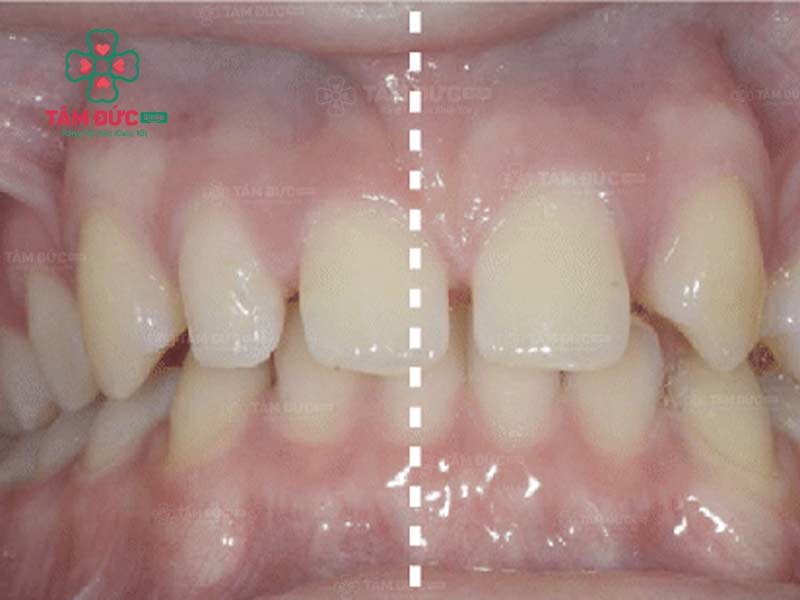

Răng lệch nhân trung là tình trạng kẽ giữa hai răng cửa không nằm thẳng với đường nhân trung. Đường nhân trung là một đường rãnh nhỏ nằm ở giữa mũi và môi trên. Ở người bình thường, kẽ giữa hai răng cửa sẽ nằm ngay trên đường nhân trung. Tuy nhiên, trong một số trường hợp, kẽ giữa hai răng cửa có thể lệch sang trái hoặc phải so với đường nhân trung.

Cách nhận biết Quý khách đang bị lệch nhân trung:

• Nhìn trực tiếp: Quý khách hãy nhìn trực tiếp khuôn mặt của mình trong gương. Nếu Quý khách thấy kẽ giữa hai răng cửa lệch sang trái hoặc phải so với đường nhân trung thì đó là dấu hiệu bị lệch đường giữa.

• Sử dụng thước đo: Quý khách hãy dùng thước đo để đo khoảng cách giữa kẽ hai răng cửa và đường nhân trung. Nếu khoảng cách này không bằng nhau thì đó là dấu hiệu của lệch nhân trung.